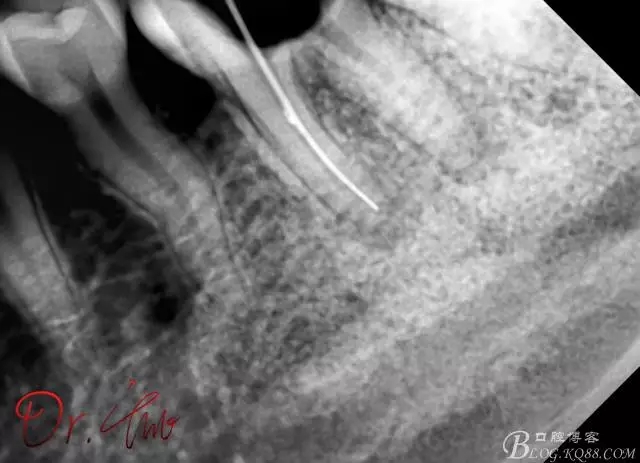

拍片確定長度

640.webp (1).jpg